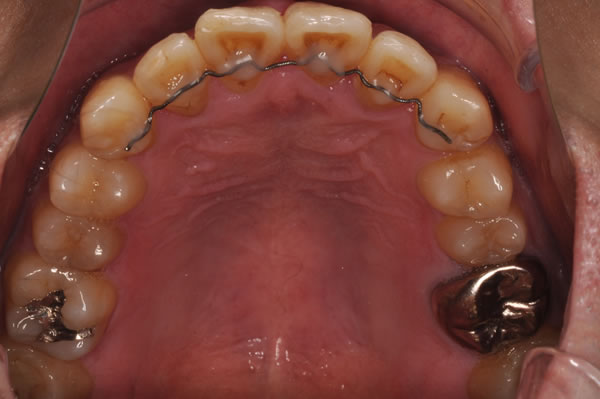

唇側矯正の治療例

反対咬合症例

治療前(初診)

治療後